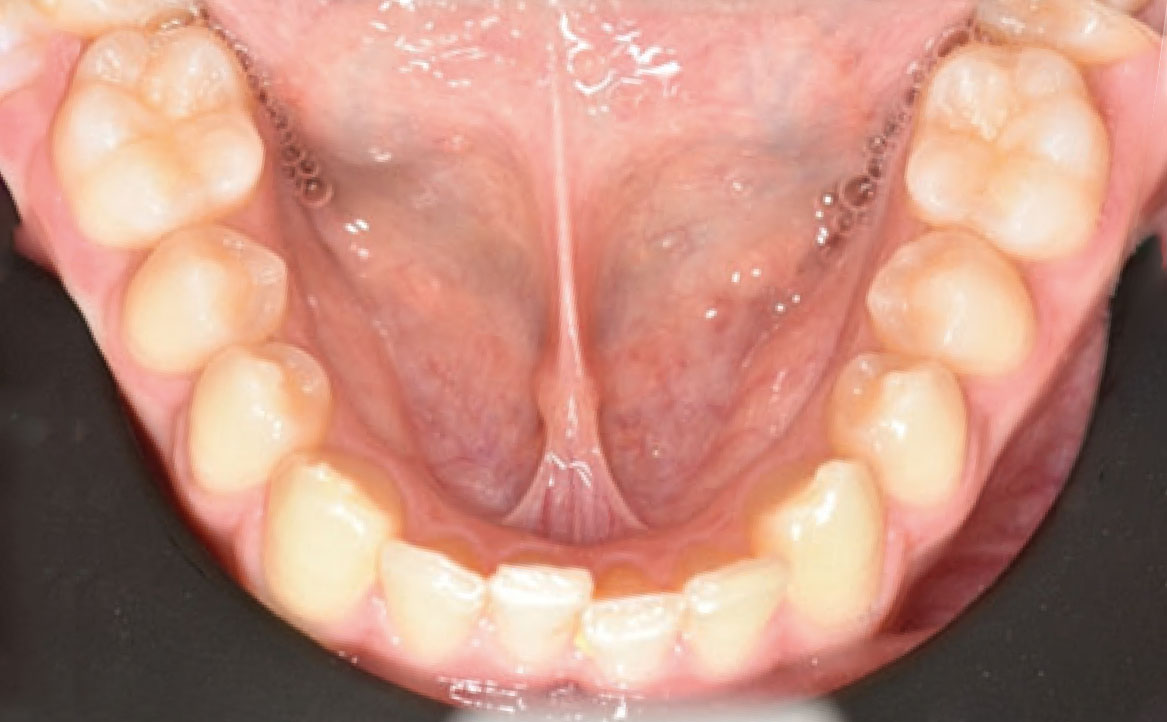

Il paziente si è presentato per la sua prima visita presso il reparto di Odontoiatria e Protesi Dentaria dell’Ospedale Vita-Salute San Raffaele diretto dal prof. E. F. Gherlone. All’esame obiettivo era evidente una malocclusione scheletrica e dentale di classe II associata a morso profondo e lieve affollamento anteriore superiore. In particolare, sono stati segnalati: rapporti occlusali di classe II, morso profondo, perdita di overjet, contrazione dell’arcata superiore e inferiore con leggero affollamento (fig. 1a-f). La richiesta del paziente era quella di migliorare l’estetica dei denti anteriori con allineatori invisibili di tipo Invisalign. Tuttavia, sia il paziente che il genitore sono stati informati che, per ragioni di efficacia e risoluzione del problema, era necessario agire anche a livello di funzionalità e risoluzione della malocclusione.

In primo luogo, sono stati prescritti entrambi gli esami radiografici ortodontici: OPT e teleradiografia latero-laterale del cranio (fig. 2a-b). Successivamente, in accordo con il genitore, è stata concordata una terapia ortodontica in due tempi. L’inizio della terapia è stato effettuato con Carriere Motion ed elastici di classe II, con l’obiettivo di migliorare la classe molare (fig. 2c-e).